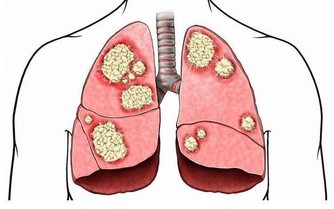

人體腎臟具有強大的代償功能,只要腎功能喪失不超過75%,仍能保持人體內環境的穩定。

所以,慢性腎衰病人早期常無明顯臨床症狀,往往容易誤診、漏診,使腎衰病人失去最佳的治療時機。

主要原因是,隨著腎功能的減退,腎臟的溶質清除率下降和某些肽類激素的滅活減少,造成多種毒素在血液和組織中蓄積,最常見的毒素就是尿素等。

在口腔中,因為唾液中的尿素被分解為氨,故病人呼出的氣體有尿味。

這種氣味的濃淡隨病情的進退而變化,在病情好轉時,口中尿味淡些,病情加重時尿味變濃。